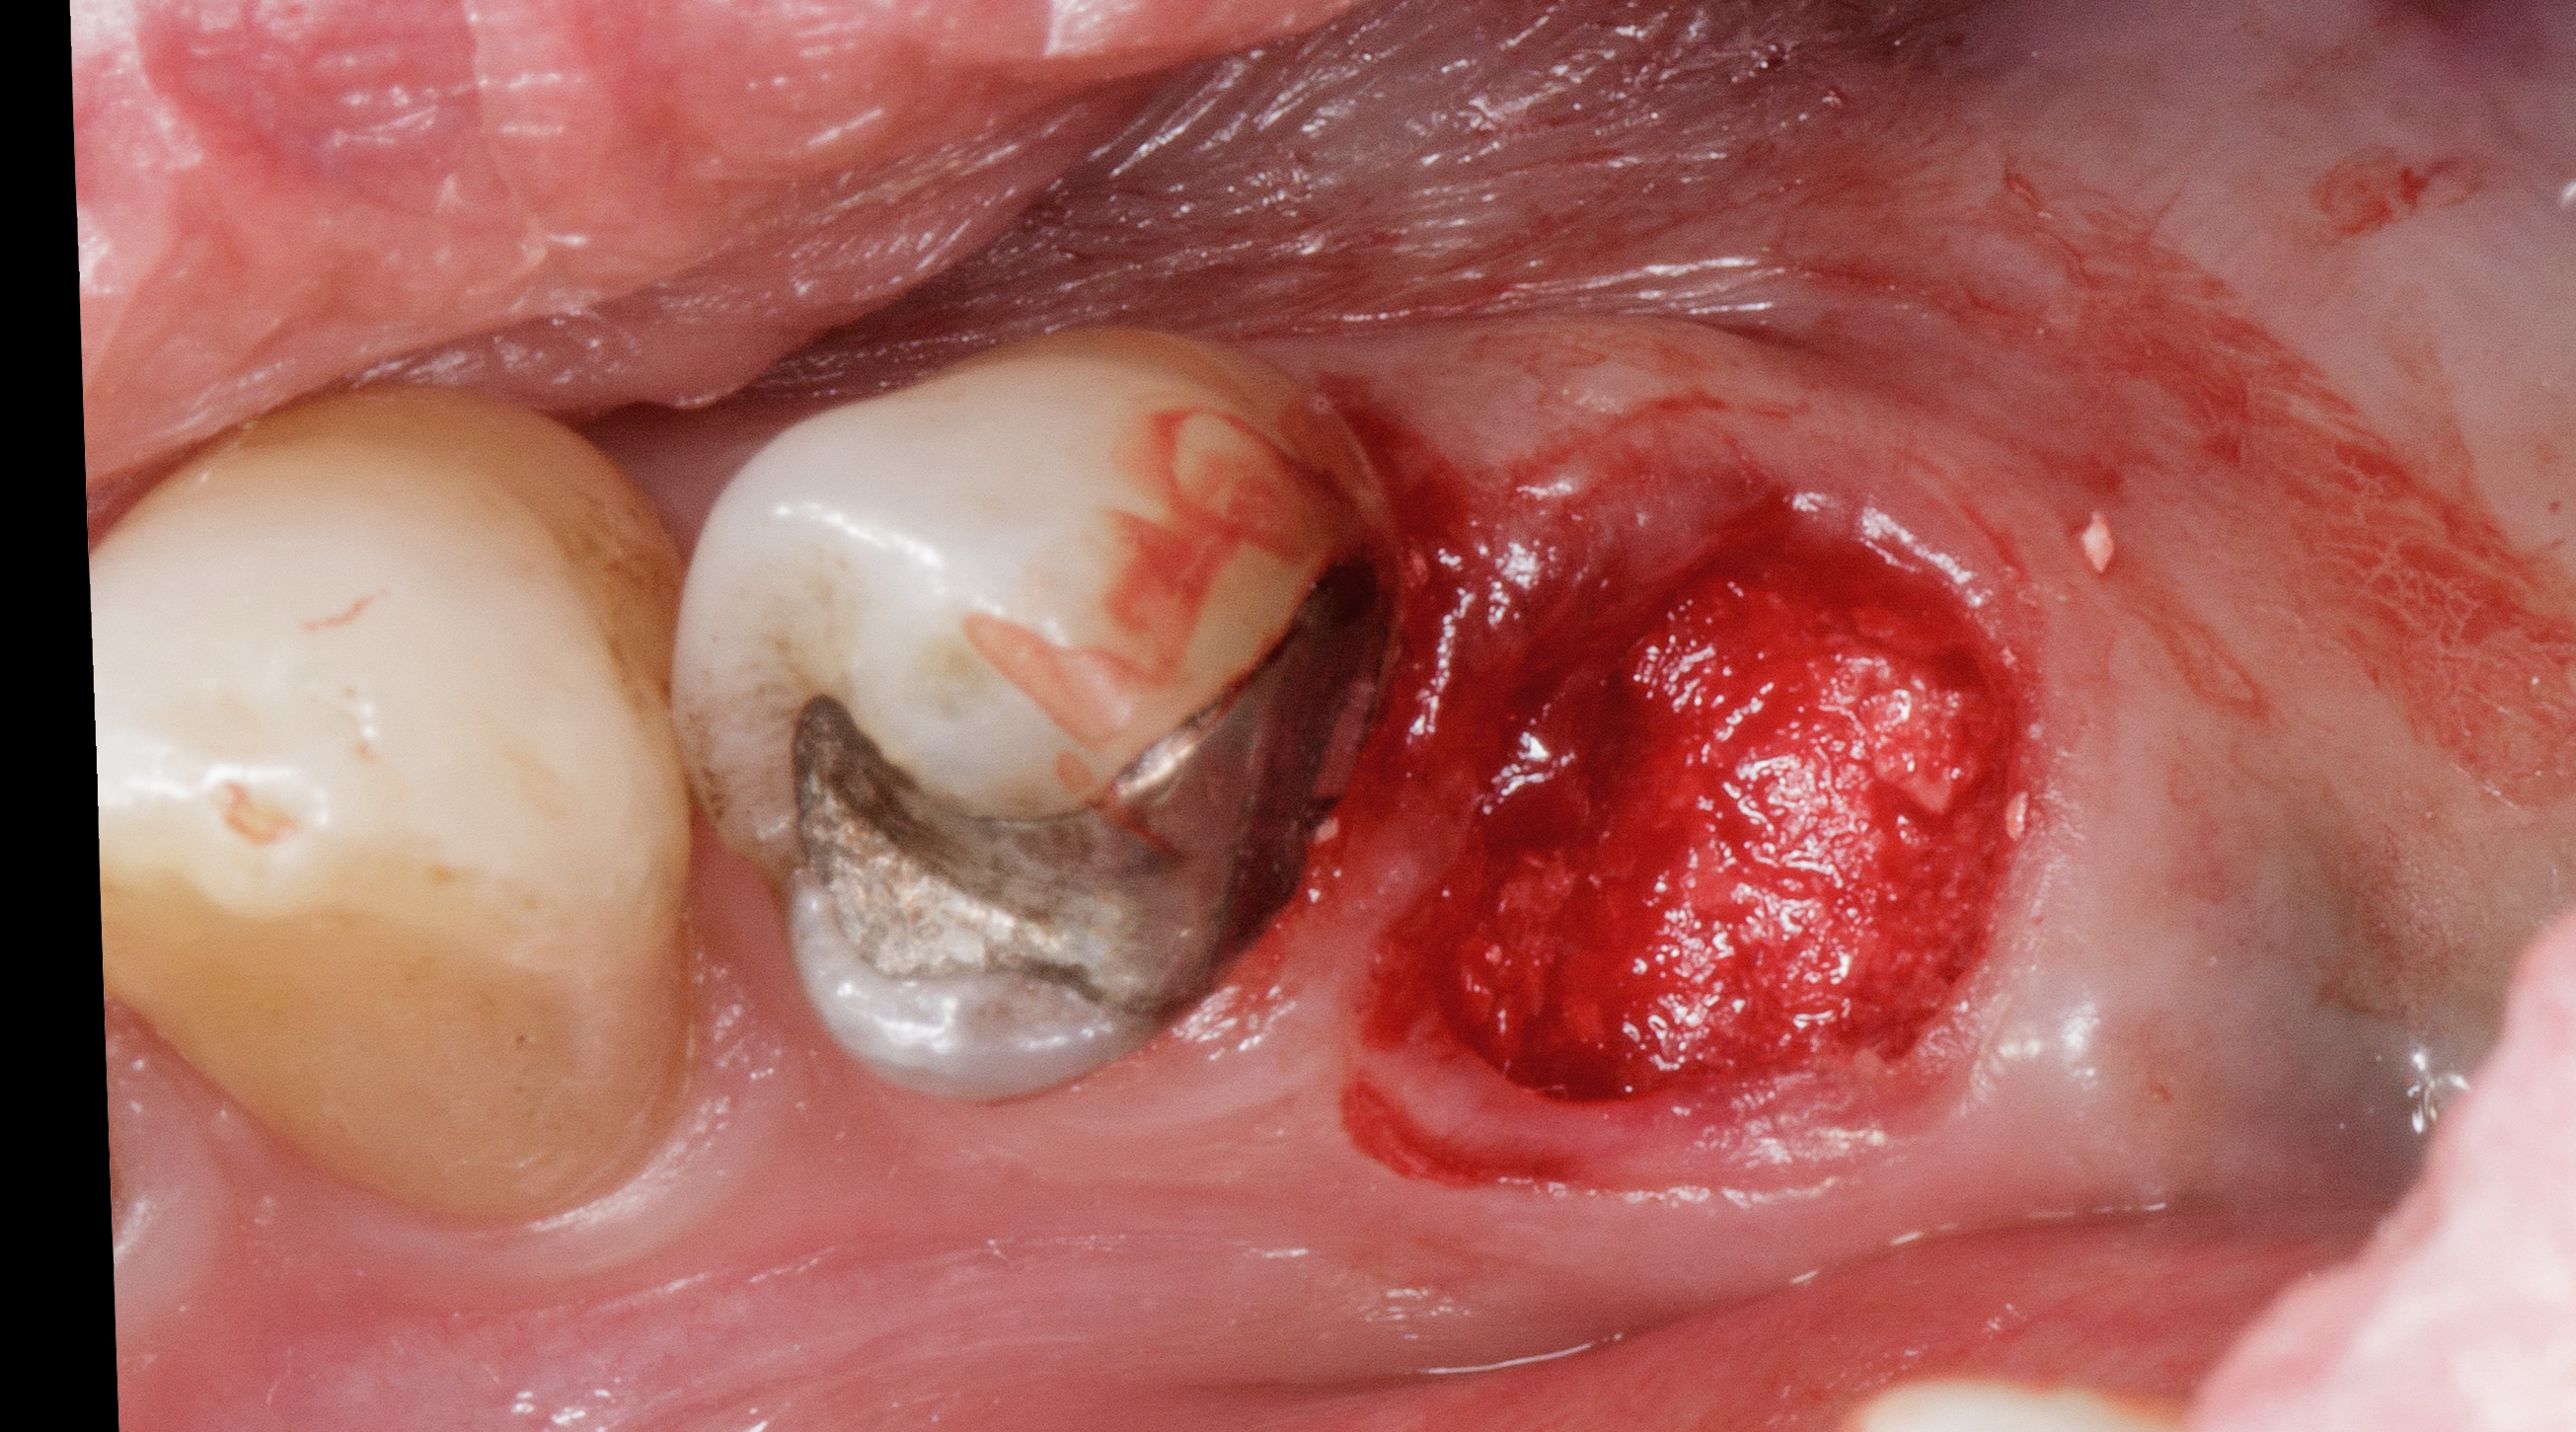

Dopo sei mesi dall’intervento di preservazione alveolare si inserisce un impianto differito in posizione 4.5.

Dopo esecuzione di lembo mucoperiosteo con una incisione di prolungamento mesiale a preservazione papillare, si osserva la presenza di tessuto osseo compatto in posizione premolare.

La corticale vestibolare e crestale non è ancora completamente formata, ma la visione in senso occlusale mostra come il tessuto osseo, che è ancora in fase di mineralizzazione, sia oltre il limite del bone housing dell’alveolo originario.

Si è ottenuta una preservazione del volume osseo oltre il 100% (Figure 18-19).

Il tunnel implantare è molto vascolarizzato. Viene inserito un impianto Neoss Tapered 4,5x11 mm, bone level, con torque di inserimento di 60 Ncm e ISQ 75 (Figure 20-22).